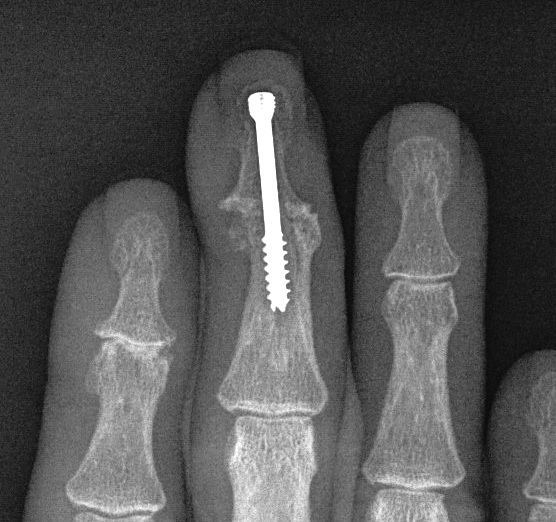

DIPJ Arthrodesis

Position

- 15 - 20o flexion

A. Headless compression screw